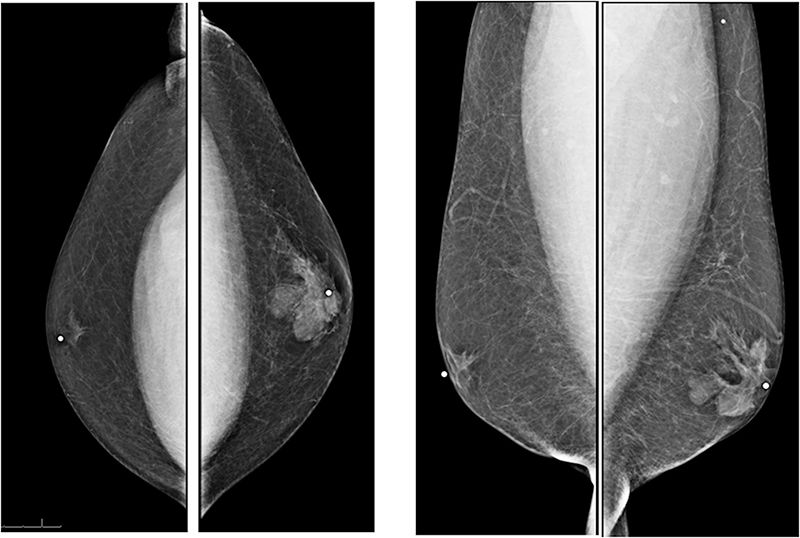

52-year-old asymptomatic female with family history of breast cancer presents for annual mammogram.

Adding ultrasound and/or tomosynthesis to digital mammography increases cancer detection.